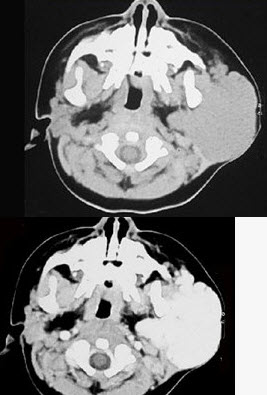

1岁女孩,左耳垂下进行性增大肿块3个月,触之质软,下面是其颈部CT检查结果,其中左图是普通扫描,右图是增强扫描。请问,患者最可能的诊断是()。

A、腮腺混合瘤

B、腮腺腺样囊性癌

C、腮腺血管瘤

D、腮腺淋巴结结核

E、腮腺黏液表皮样癌

C